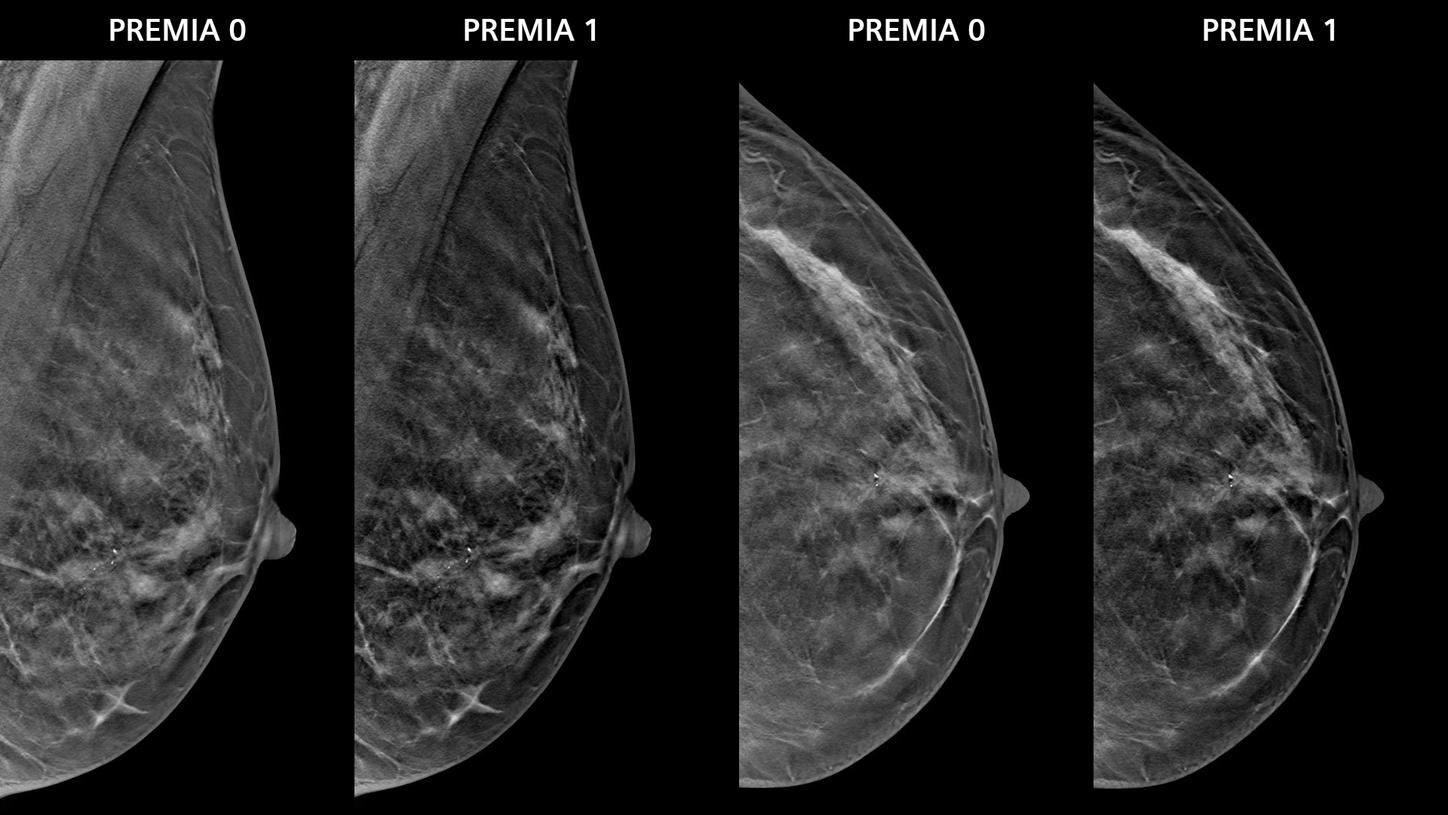

• PREMIA image reconstruction:

Improved image reconstruction framework

• Reduce artifacts and enhance visibility of calcifications and lesions

• Comfortable transition from 2D and narrow-angle systems, thanks to customizable image impressions

• Boost synthetic mammogram sharpness, thanks to AI-powered noise reduction